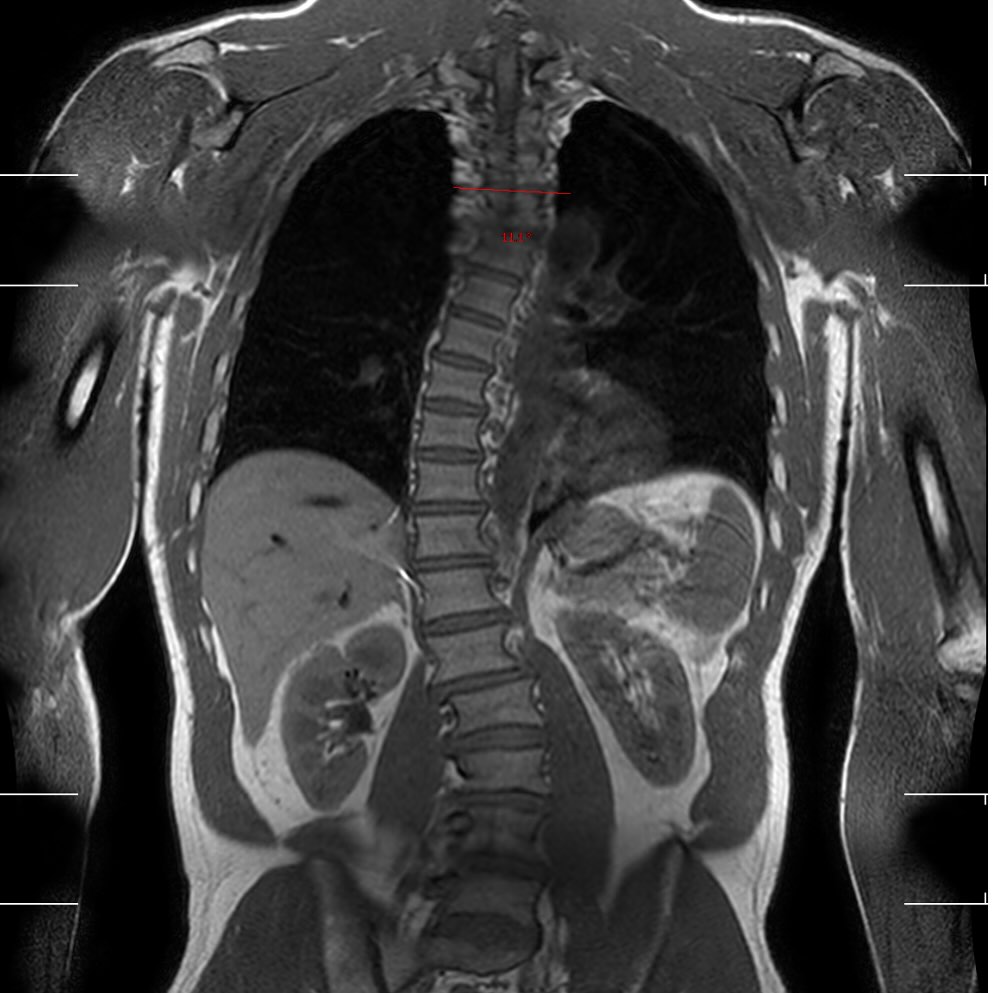

Ele já conquistou onze vezes o campeonato mundial de surfe, o que lhe deu o título de “Lenda do Surfe”. Atualmente com 53 anos de idade, Kelly Slater compartilhou em seu perfil no Instagram imagens de uma tomografia que mostra sua coluna vertebral com o diagnóstico de escoliose, situação com a qual ele convive há cinco anos.

“Minha escoliose (...) é um problema sério. Mostrar minha coluna parece super pessoal, pois é uma loucura ver a curvatura com a qual lidei todos esses anos, mas acho importante que as pessoas saibam que todos nós lidamos com doenças físicas e podemos encontrar maneiras de minimizar seus impactos”, disse Slater na publicação.

A escoliose consiste em uma curvatura lateral anômala da coluna vertebral. Popularmente é conhecida como “coluna em S”, devido ao formato da curva.

O diagnóstico depende de avaliação e exames médicos, como raio-X e tomografia, a fim de possibilitar o tratamento para a correção e controle do desvio, o que vai depender da gravidade do problema.